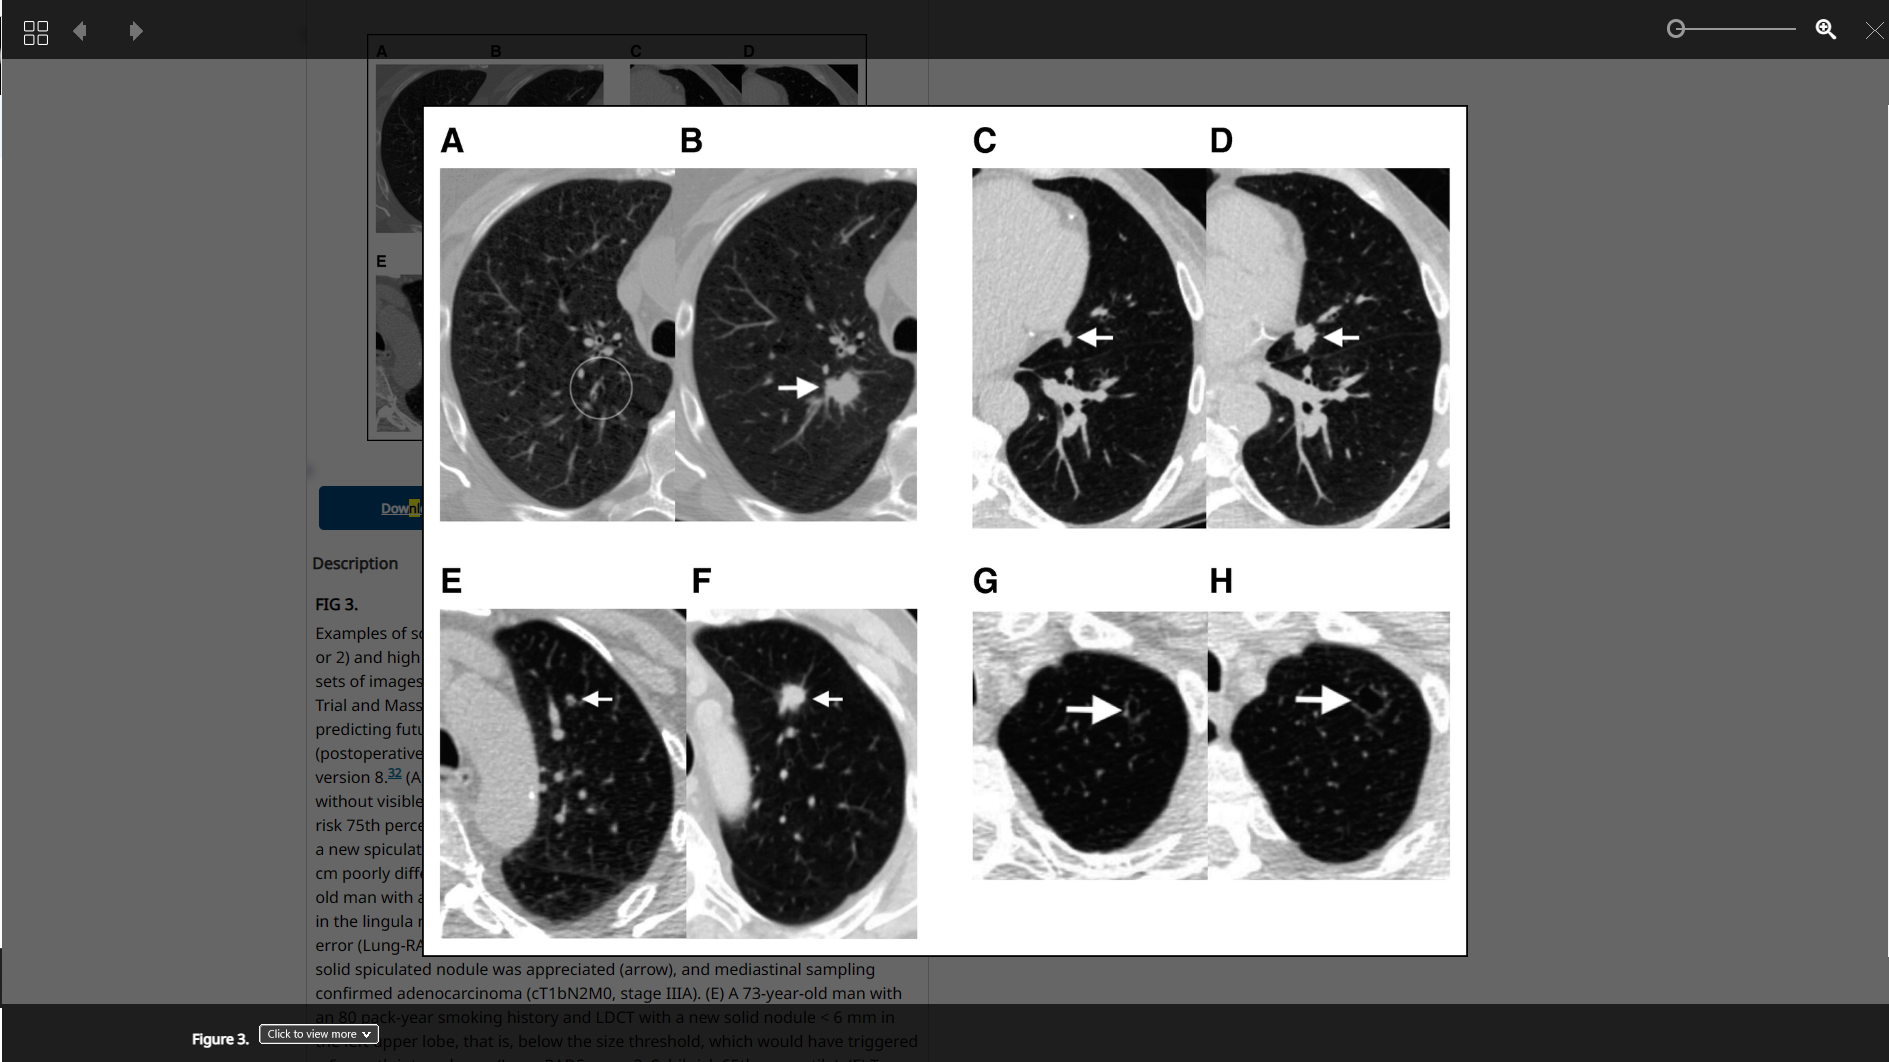

Studie: Deep-Learning-Model "Sybil" soll bei Lungenkrebsfrüherkennung helfen

Mit dem Deep-Learning-Model "Sybil" ist es Forschern gelungen, das Lungenkrebsrisiko bis zu sechs Jahre vor der Erkrankung anhand eines CT-Scans zu bestimmen.

heise.de/news/Studie-Deep-Lear…

#DeepLearning #DigitalHealth #Sybil